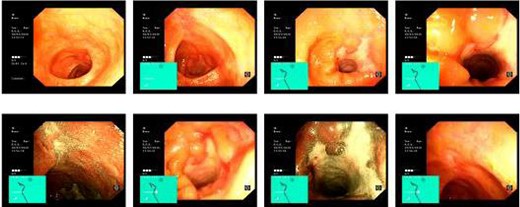

The patient was commenced on total parenteral nutrition for 10 days prior to surgery. At laparotomy, the fistulous mass involving the distal stomach, proximal transverse colon and a shrunken gallbladder with no obvious calculi, was dissected en bloc and resected (Fig. 5). This involved a right hemicolectomy, cholecystectomy and distal gastrectomy, with Roux-en-Y reconstruction to the stomach and an ileo-transverse anastomosis.

Specimen demonstrating en bloc distal gastrectomy (red arrow), cholecystectomy (shrunken and fibrosed to gastric antrum) and extended right hemicolectomy (blue arrow).